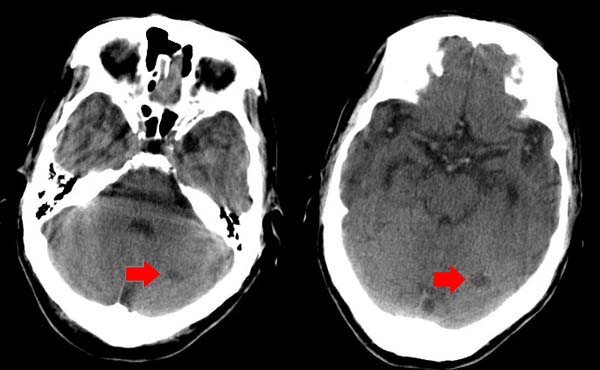

左颞枕叶交界区的类圆形高密度区首先考虑脑膜瘤卒中,病人左侧小脑半球的还有多个囊性低密度,要考虑同时伴有梗塞的可能。

小脑左侧是不是还有个小病灶???

左小脑梗塞;左顶部脑血管畸形可能;